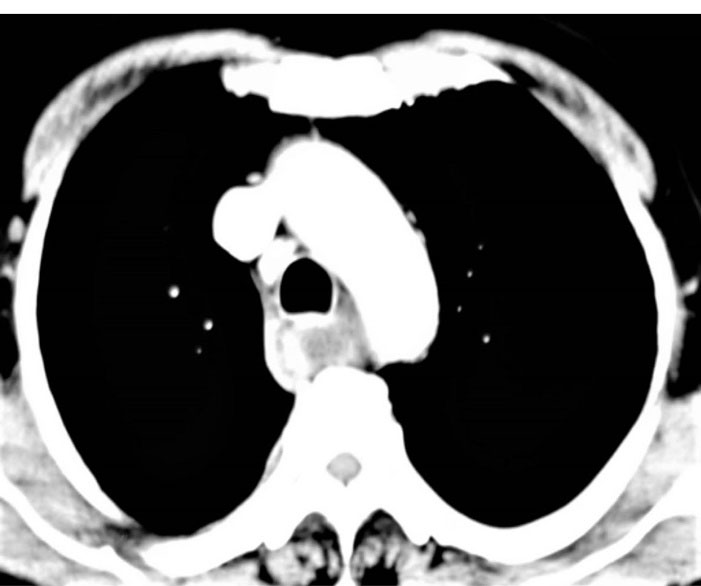

The heparin was stopped. Aspirin was continued throughout but clopidogrel was stopped and added at the time of discharge After initial resuscitation, a UGIE was done, which showed a bluish discoloration in the wall of the esophagus, from middle to the lower part (). There was no active bleed present.A Computed Tomography (CT) Angiography was done which was consistent with the diagnosis of EIH (). The clinical diagnosis of EIH is important in ruling out other differentials, which may have worse prognosis.

Figure 2.

CECT Chest of the patient at the level of arch of aorta showing a dilated oesophagus with eccentric heterogeneously hypodense esophageal wall thickening suggestive of the hematoma

The diagnosis of EIH is established by endoscopy and radiology. In Upper GI Endoscopy, the haematoma is seen as a bluish discoloration located most commonly in the lower part of the esophagus as it is deficient in striated muscles and other supporting structures.2 Radiological investigations include CECT, Magnetic Resonance Imaging (MRI), and CT/MRI Angiography. The typical appearance on CT is of an eccentric hyperattenuating mass in the wall of the esophagus.8 MRI may be used to better delineate the soft tissue planes.